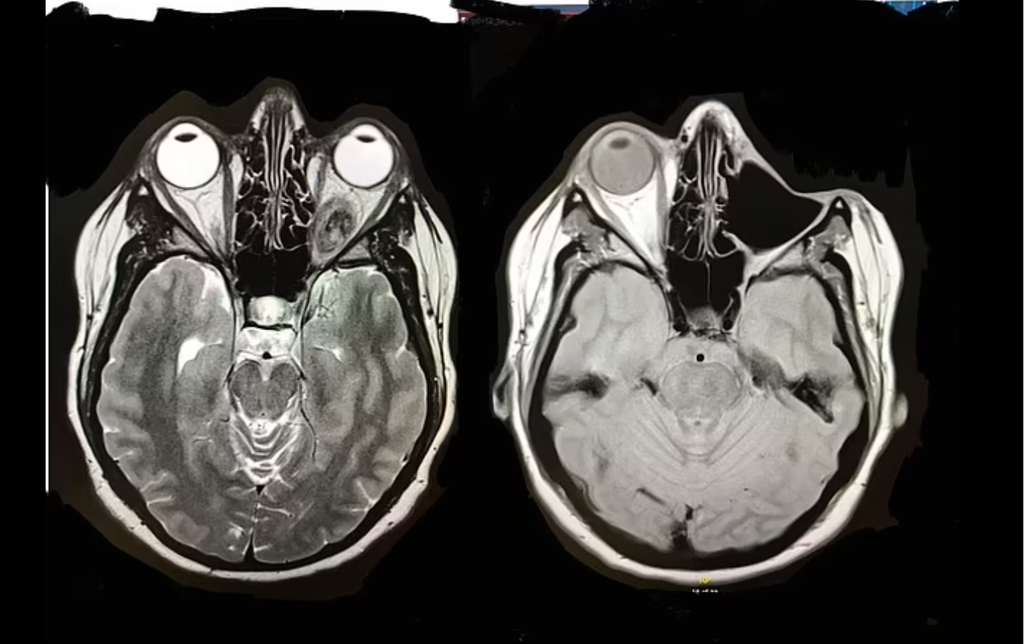

据《每日邮报》报导,库辛丝在2018年发现自己的左眼明显凸出,于是到急症室就诊,经过医生的判断以及核磁共振的检查后,发现她眼睛后面长了一个大肿瘤,医生把她过去的自拍照判断,这颗肉瘤在她约17岁时就存在,并随著时间逐渐长大。告诉她罹患罕见的间叶型软骨肉瘤(mesenchymal chondrosarcoma)。医生指库辛丝是唯一一名在英格兰患有此病患的人,并叮嘱她「千万不要到google搜索」。